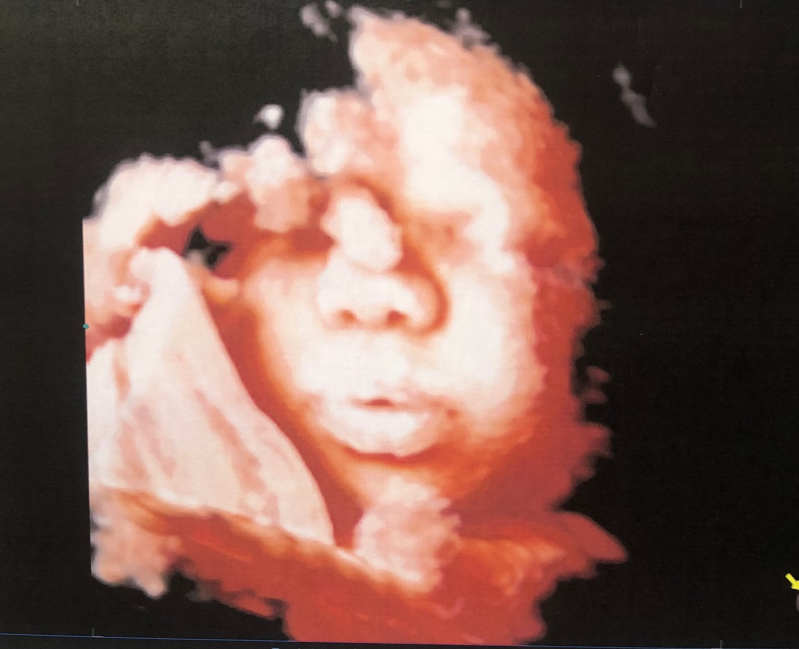

Lo studio medico Sciuto, rivolgendosi alle pazienti con professionalità e disponibilità, si occupa della cura e del trattamento delle problematiche ginecologiche ed ostetriche impiegando adeguate strumentazioni diagnostiche.

- Ecografia ostetrica;

- Ecografia ginecologica (transaddominale e transvaginale);

- Diagnosi prenatale: